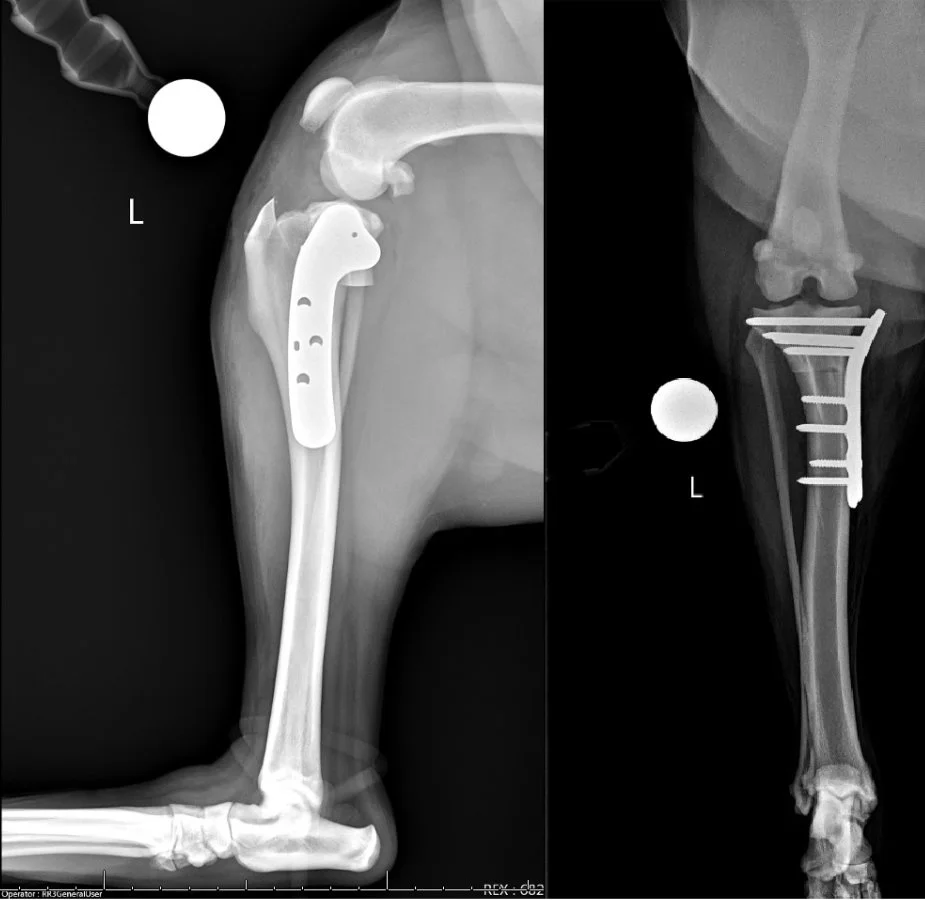

TPLO (Tibial Plateau Leveling Osteotomy)

Surgery for dog ACL (also known as CCL) repair.

TPLO is the most recommended surgical correction for ACL tear in North America. First performed in 1993, it has become the preferred surgical stabilization for dogs with ACL/CCL tears. Dr. Curtis has extensive experience in orthopedic surgeries, including TPLO. If your dog is suffering from an ACL injury, please contact us so we can get them on the road to recovery!